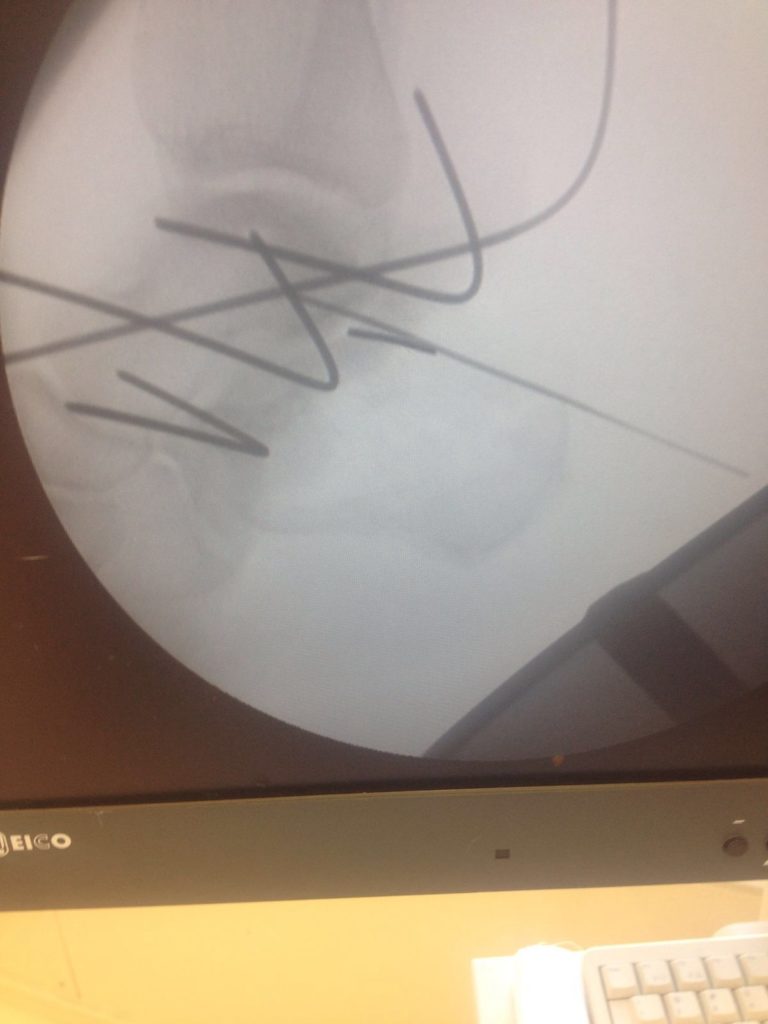

Операция – открытая репозиция, остеосинтез пяточной кости пластиной с костной ксенопластикой материалом «Остеоматрикс». На контрольных снимках в три месяца имеется консолидация перелома, миграции фиксатора нет, имеется остеоинтеграция ксенопластического материала.